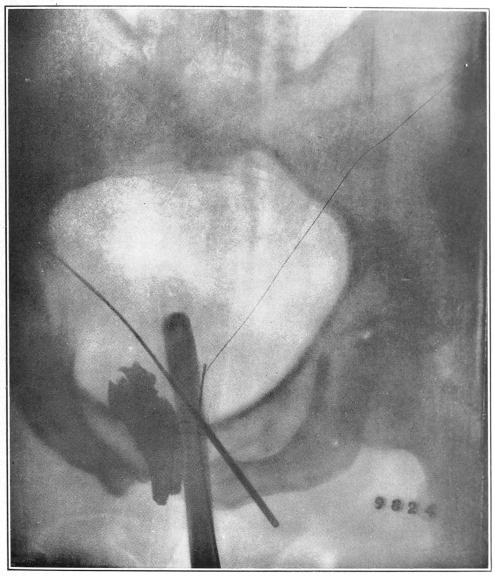

Nine Radiograph Illustrations Showing Mucus Channels and Cavities200

CHAPTER XXV.

Chronic Mucous Proctitis and Sigmoiditis—Usually Diagnosed as Chronic Mucous Colitis202